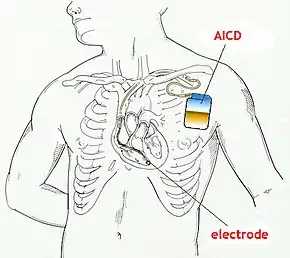

An implantable cardioverter-defibrillator (ICD) or automated implantable cardioverter defibrillator (AICD) is a device implantable inside the body, able to perform defibrillation, and depending on the type, cardioversion and pacing of the heart. The ICD is the first-line treatment and prophylactic therapy for patients at risk for sudden cardiac death due to ventricular fibrillation and ventricular tachycardia.[1]

The process of implantation of an ICD system is similar to implantation of a artificial pacemaker. In fact, ICDs are composed of an ICD generator and of wires. The first component or generator contains a computer chip or circuitry with RAM (memory), programmable software, a capacitor and a battery; this is implanted typically under the skin in the left upper chest. The second part of the system is an electrode wire or wires that, similar to pacemakers, are connected to the generator and passed through a vein to the right chambers of the heart. The lead usually lodges in the apex or septum of the right ventricle.[6]

Just like pacemakers, ICDs can have a single wire or lead in the heart (in the right ventricle, single chamber ICD), two leads (in the right atrium and right ventricle, dual chamber ICD) or three leads (biventricular ICD, one in the right atrium, one in the right ventricle and one on the outer wall of the left ventricle). The difference between pacemakers and ICDs is that pacemakers are also available as temporary units and are generally designed to correct slow heart rates, i.e. bradycardia, while ICDs are often permanent safeguards against sudden life-threatening arrhythmias.

Initially ICDs were implanted via thoracotomy with defibrillator patches applied to the epicardium or pericardium. The device was attached via subcutaneous and transvenous leads to the device contained in a subcutaneous abdominal wall pocket. The device itself acts as an electrode. Most ICDs nowadays are implanted transvenously with the devices placed in the left pectoral region similar to pacemakers. Intravascular spring or coil electrodes are used to defibrillate. The devices have become smaller and less invasive as the technology advances. Current ICDs weigh only 70 grams and are about 12.9 mm thick.